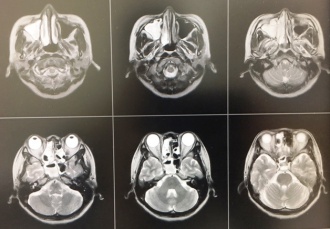

【副鼻腔炎(蓄膿症)による頭痛】

副鼻腔炎と言えば、頬や目の奥の痛みと鼻水・鼻づまりが一般的ですが、頭痛の原因にもなります。炎症の部位によっては、おでこや後頭部が痛くなる場合があります。

当院はMRI検査で診断しています。治療は抗生剤を長期内服することで改善することが多く、当院でも行っています。